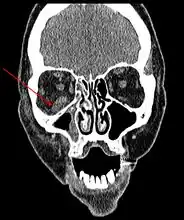

Imaging

Imaging is often performed, such as CT scan of lungs and sinuses.[38] Signs on chest CT scans, such as nodules, cavities, halo signs, pleural effusion and wedge-shaped shadows, showing invasion of blood vessels may suggest a fungal infection, but does not confirm mucormycosis.[16] A reverse halo sign in a person with a blood cancer and low neutrophil count, is highly suggestive of mucormycosis.[16] CT scan images of mucormycosis can be useful to distinguish mucormycosis of the orbit and cellulitis of the orbit, but imaging may look identical to those of aspergillosis.[16] MRI may also be useful.[39]

CT head (axial): invasion of right maxillary sinus (presented with double vision, swollen painful eye). -

CT head (coronal) of same person. -